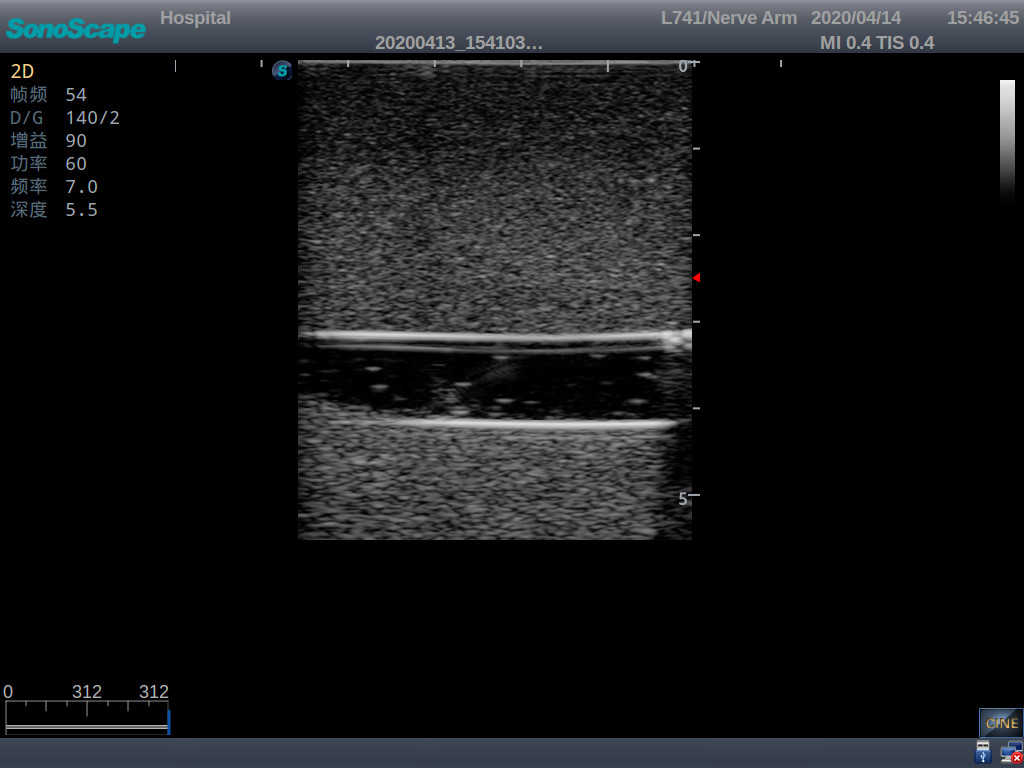

2) It can be used by real ultrasound machines

3) Clear and real images of the tissues and organs (basilic vein and superior vena cava)

5) Observe the guide wire marches